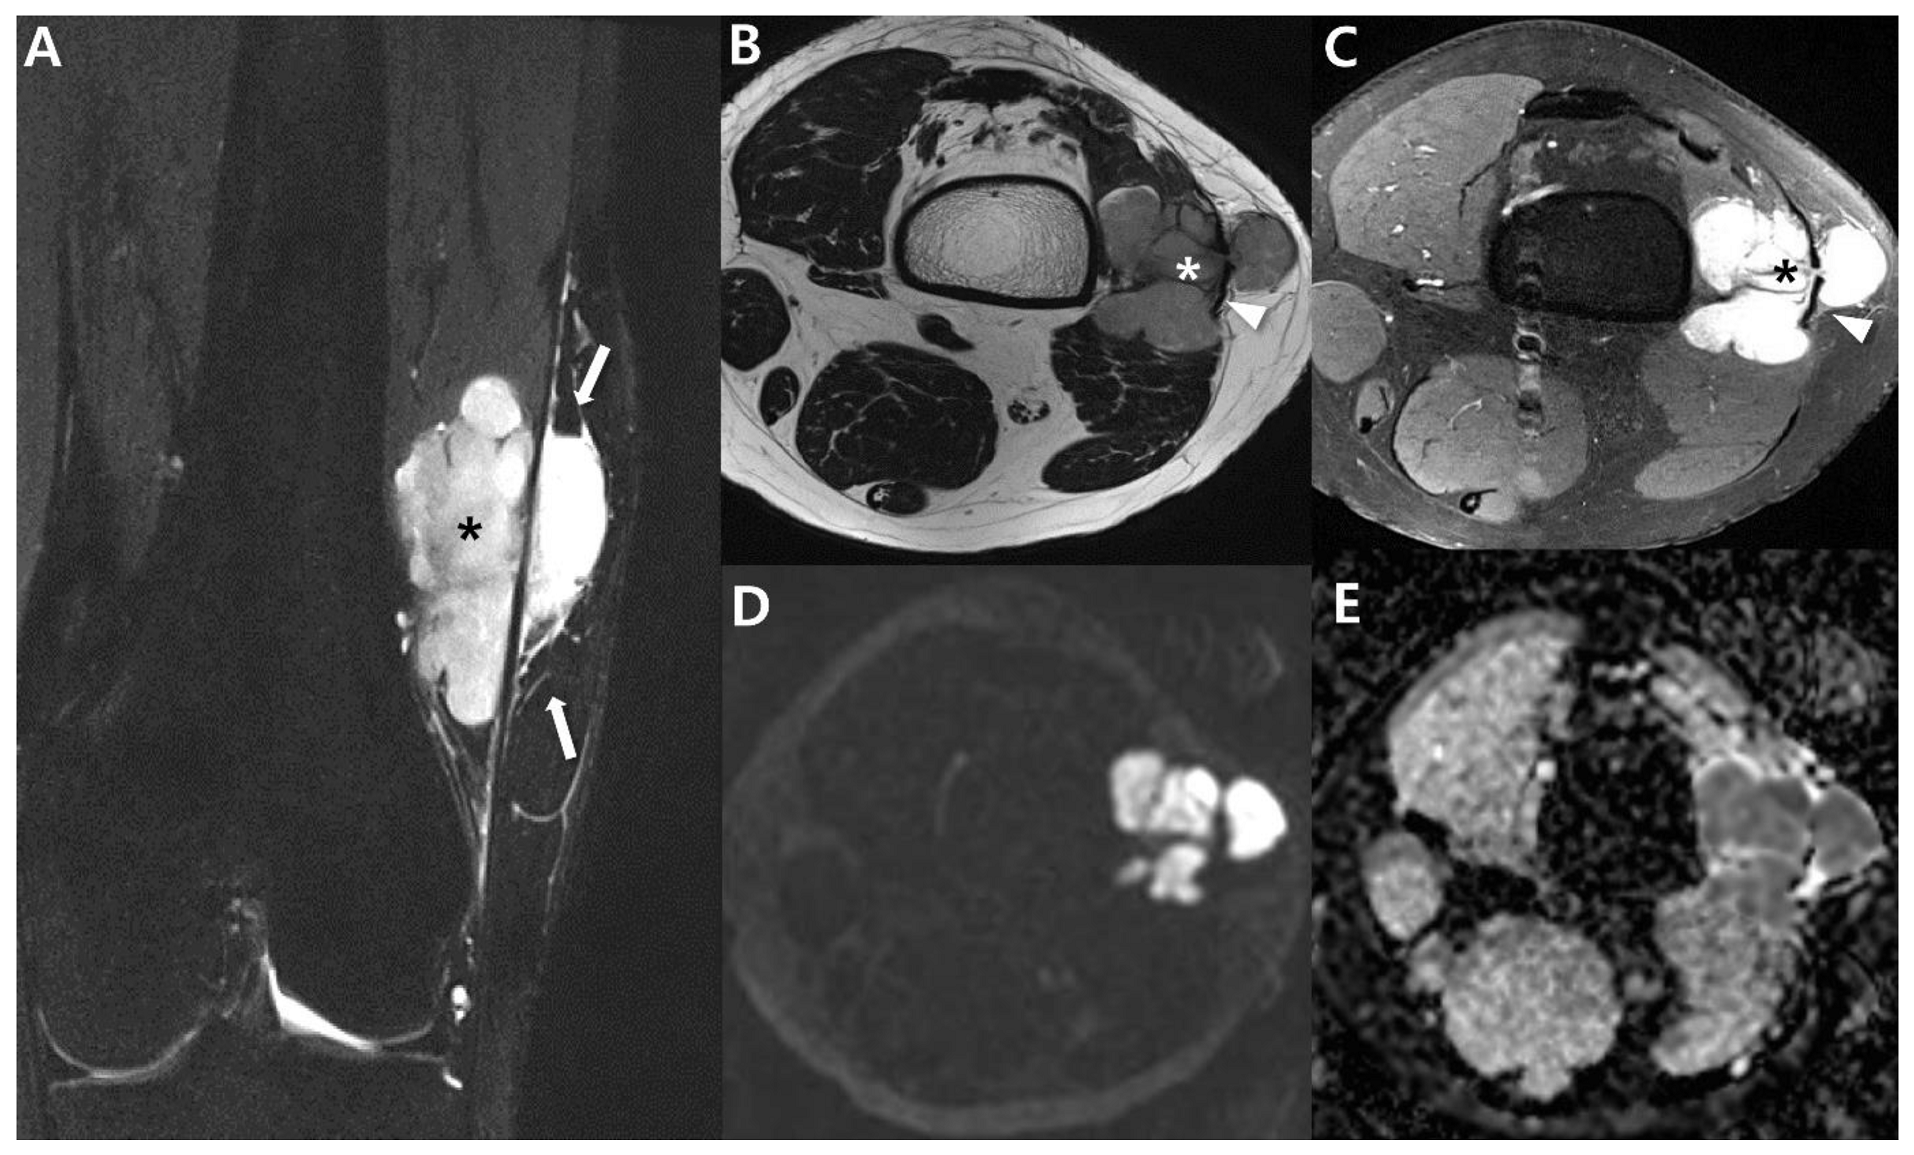

2.4. Magnetic Resonance Imaging (MRI)

2.5. Advanced MRI

| Imaging features | Intratumoral hemorrhage (fluid-fluid levels) | Poor |

| Triple sign on MRI | ||

| Bowl-of-grapes appearance on MRI | ||